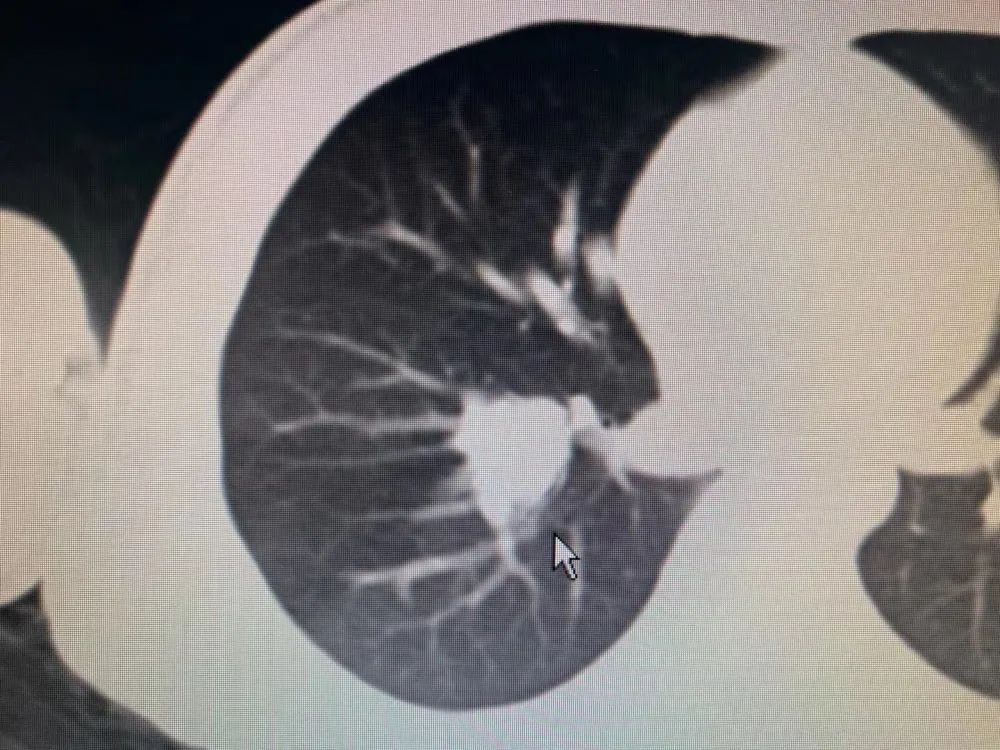

胸腹CT示:“右下肺背段結(jié)節(jié),葉間氣管旁腫大淋巴結(jié)來(lái)源可能,右下肺少許纖維條索。上腹部未見(jiàn)明確占位性病變”,纖支鏡檢查提示:“右下肺基底段支氣管開(kāi)口見(jiàn)結(jié)節(jié)狀腫物,表面充血,質(zhì)地脆”鏡下活檢示(右下葉基底段開(kāi)口結(jié)節(jié)狀腫物活檢):結(jié)合免疫組化,考慮為涎腺源性腫瘤。

5月24日韞狄在父親的陪同下來(lái)了廣州復(fù)大腫瘤醫(yī)院,隔天韞狄做了胸部、上腹部CT平掃+增強(qiáng):1、考慮右肺下葉腫瘤性病變,結(jié)節(jié)大小有2.0*1.9*2.0cm,結(jié)合臨床及病理檢查。2、縱隔及右肺門(mén)多發(fā)稍大及小淋巴結(jié)。診斷為右肺門(mén)占位性病變。